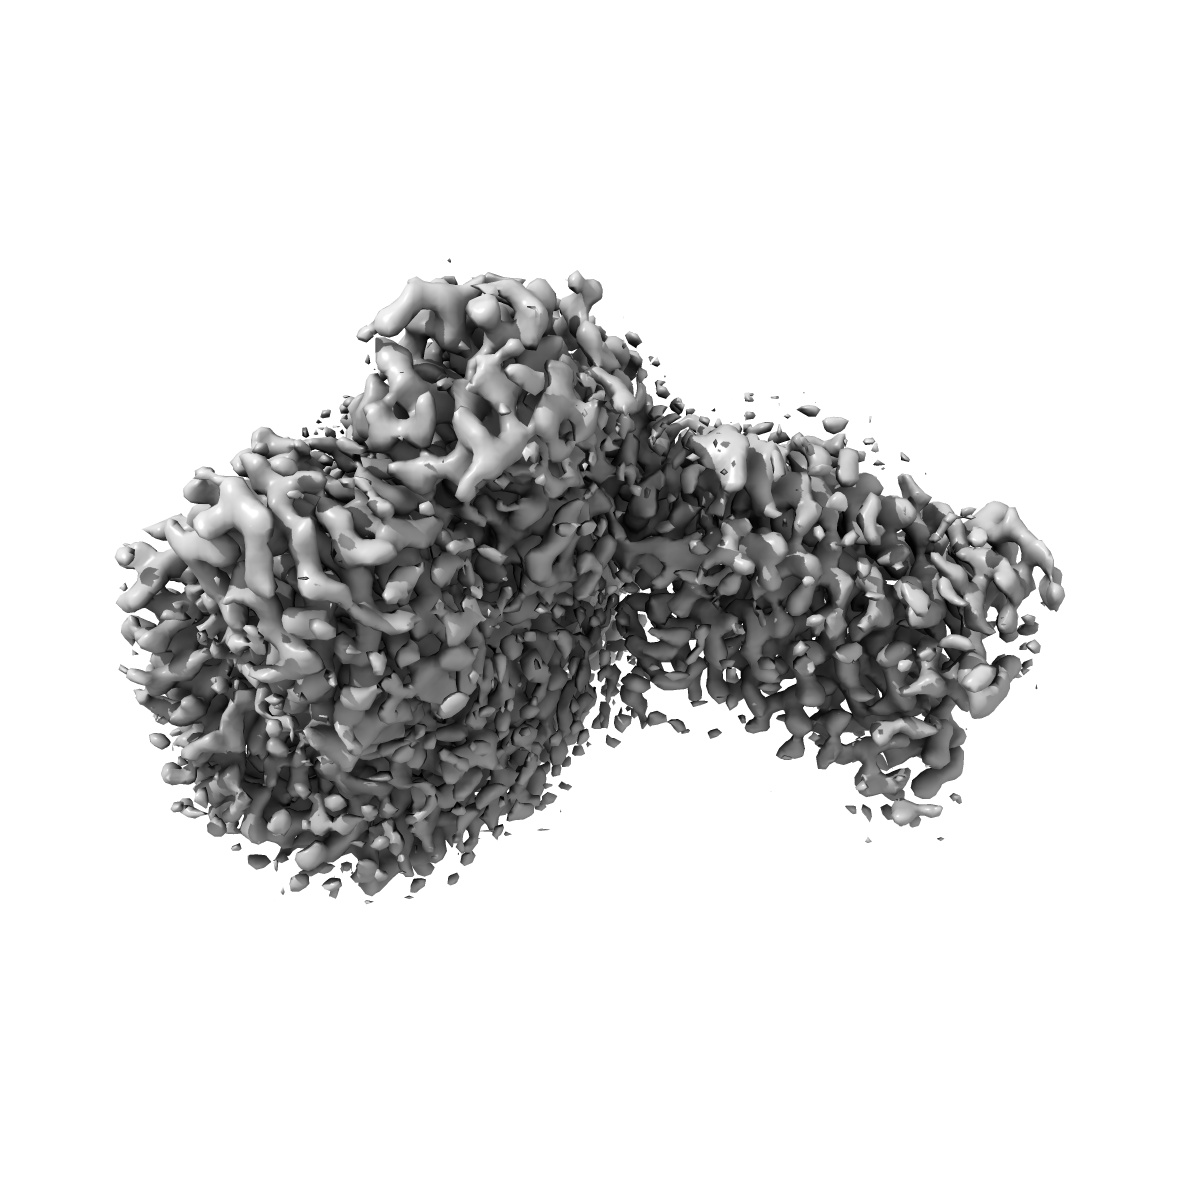

Cryo-EM structure of the imetit-bound histamine H4 receptor and Gq complex

Sample: Imetit bound histamine h4 receptor in complex with Gq

Fitted models: 7yfd

Structural insights into the agonists binding and receptor selectivity of human histamine H 4 receptor.

Im D , Kishikawa JI , Shiimura Y, Hisano H, Ito A, Fujita-Fujiharu Y , Sugita Y , Noda T, Kato T , Asada H , Iwata S

(2023) Nat Commun , 14 , 6538 - 6538